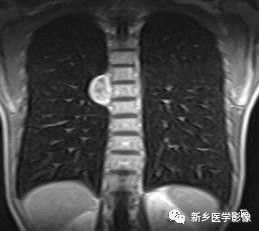

3.MRI表现:脊柱周围实质性肿块,T1WI呈等信号,与肌肉相似,T2WI略高于肌肉,部分信号不均匀,轻至中度强化。

右中纵隔神经鞘瘤CT图像

MRI冠状位T1WI图像示胸椎右旁椭圆形病灶,病灶内部呈混杂信号,边缘呈高信号。